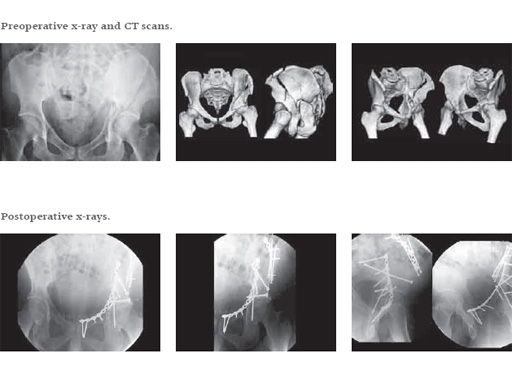

Case new pelvic set

32-year-old man (165 kg), fell 7 meter into stairwell; bilateral open tibial fractures and both column fractures variant.